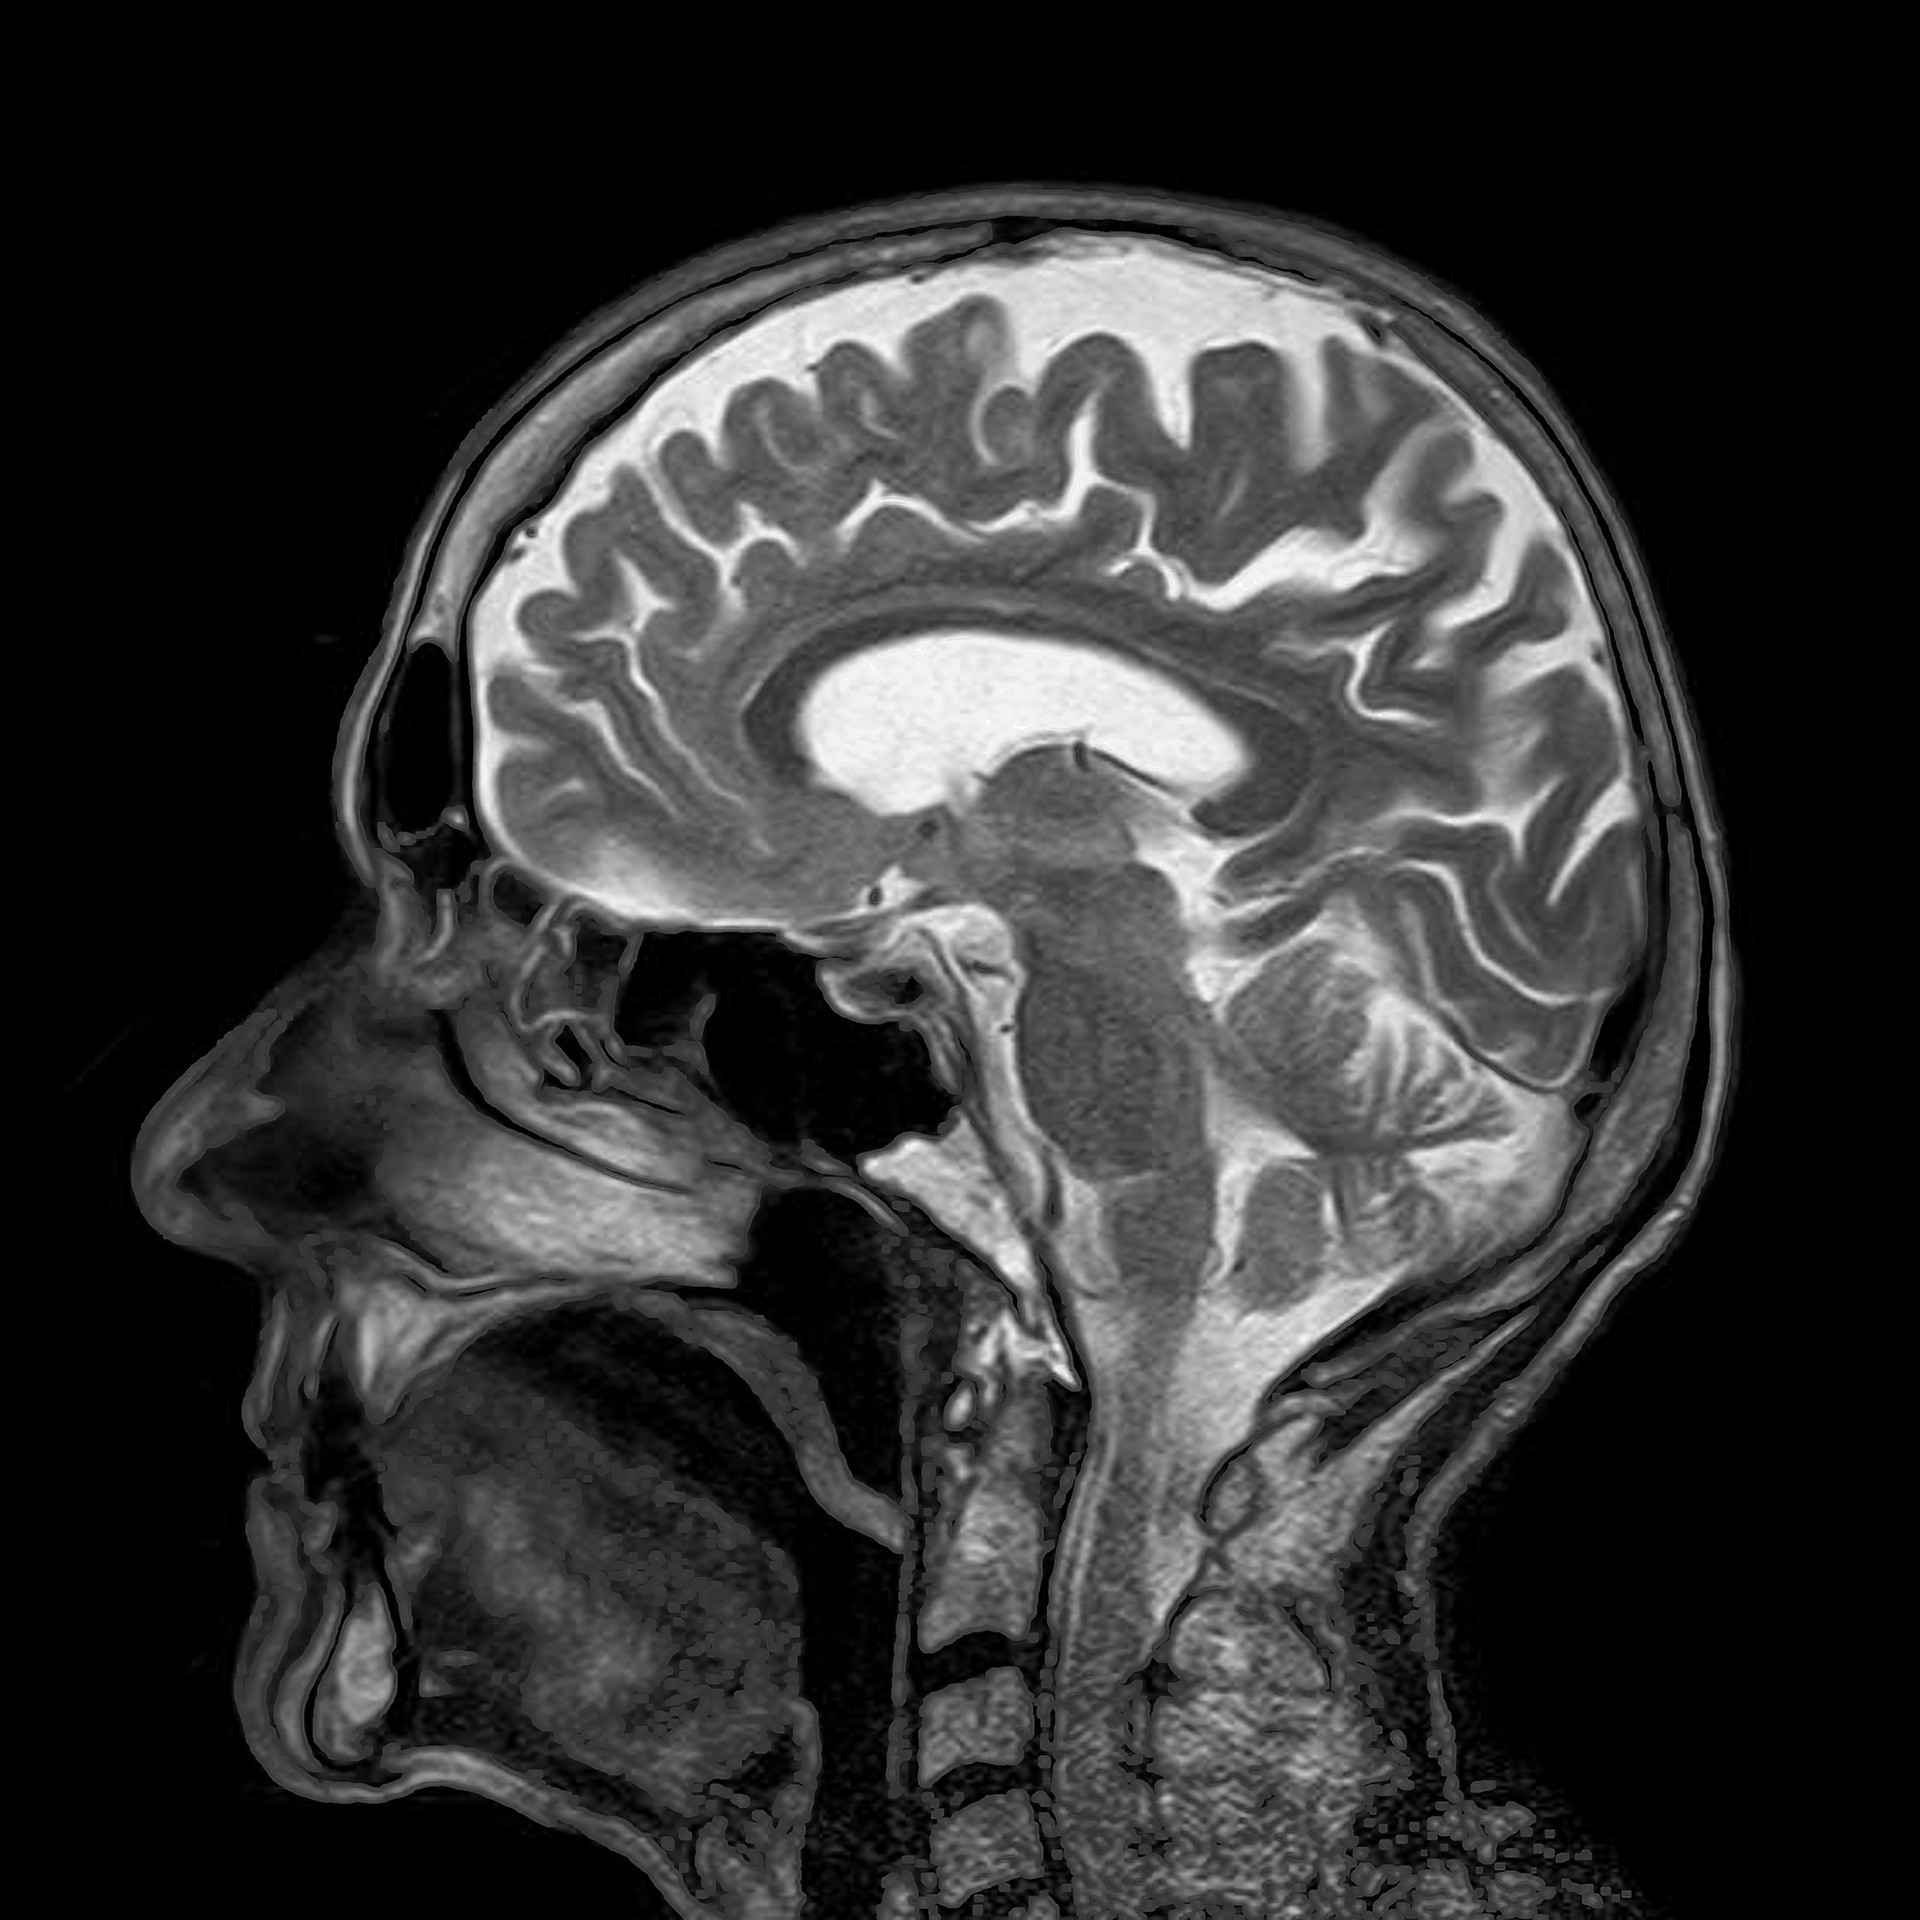

Az agysérülés külső erők hatására létrejövő szerkezeti és/vagy működési károsodás. Megnyilvánulhat tudatzavarban, emlékezetkiesésben, mentális állapotváltozásban – ködös állapot, meglassult gondolkodás -, központi idegrendszeri tünetekben – bénulás, beszédzavar, epilepszia -, valamint az agy szerkezeti károsodásában – emelték ki.